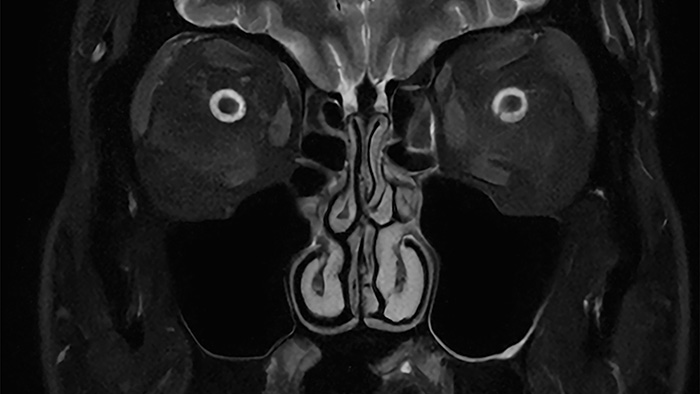

De nieuwste SmartSpeed Precise [1]-technologie verhoogt de productiviteit nog verder, waardoor scans tot drie keer sneller kunnen worden uitgevoerd [7] en de scantijd aanzienlijk wordt verkort terwijl de uitzonderlijke beeldkwaliteit behouden blijft. De kern van SmartSpeed Precise is de dual AI-engine, die zorgt voor een verbetering van 80% in de scherpte van de beelden [8], waardoor de visualisatie wordt verbeterd voor betrouwbaardere en nauwkeurigere diagnoses. Deze krachtige combinatie van snelheid en precisie zorgt ervoor dat radiologen subtiele afwijkingen duidelijker kunnen detecteren, wat uiteindelijk leidt tot betere patiëntresultaten. De nieuwe release van Philips – MR Workspace R12 [6] – introduceert een ‘zero-click’-workflow [9], die het gehele beeldvormingsproces naadloos begeleidt, van het starten van de scan tot het genereren van rapporten. Door handmatige handelingen te verminderen en de efficiëntie te optimaliseren, stelt MR Workspace R12 [6] radiologieafdelingen in staat de patiëntdoorstroming te verbeteren en achterstanden terug te dringen, waarmee tegemoet wordt gekomen aan de toenemende vraag naar snellere en nauwkeurigere beeldvorming. Een belangrijke innovatie binnen MR Workspace R12 [6] is de door AI aangestuurde SmartExam-functie, die 80% van de MR-procedures automatiseert [10], door werkzaamheden te stroomlijnen en beeldvormingsworkflows te standaardiseren.

Andere baanbrekende innovaties zijn onder andere Smart Reading [4], de eerste oplossing in de industrie die cloudgebaseerde, door AI aangestuurde kwantitatieve rapportage naadloos [11] integreert. Smart Reading maakt gebruik van geavanceerde AI-platformen zoals icobrain (icometrix) voor neurologie – inclusief detectie van de ziekte van Alzheimer – en QP-Prostate (Quibim) voor geavanceerde diagnose van prostaatkanker. Door objectieve, zeer betrouwbare diagnoses te leveren, maken deze zero-click AI-oplossingen [9] gestroomlijnde, op data gebaseerde besluitvorming mogelijk voor artsen. Met MR Workspace R12 [6], SmartSpeed Precise [1] en Smart Reading [4] blijft Philips de grenzen van AI in MRI verleggen om de efficiëntie, nauwkeurigheid en toegankelijkheid van diagnostische beeldvorming te vergroten en tegelijkertijd de weg vrij te maken voor de toekomst van autonome MR-scanning.